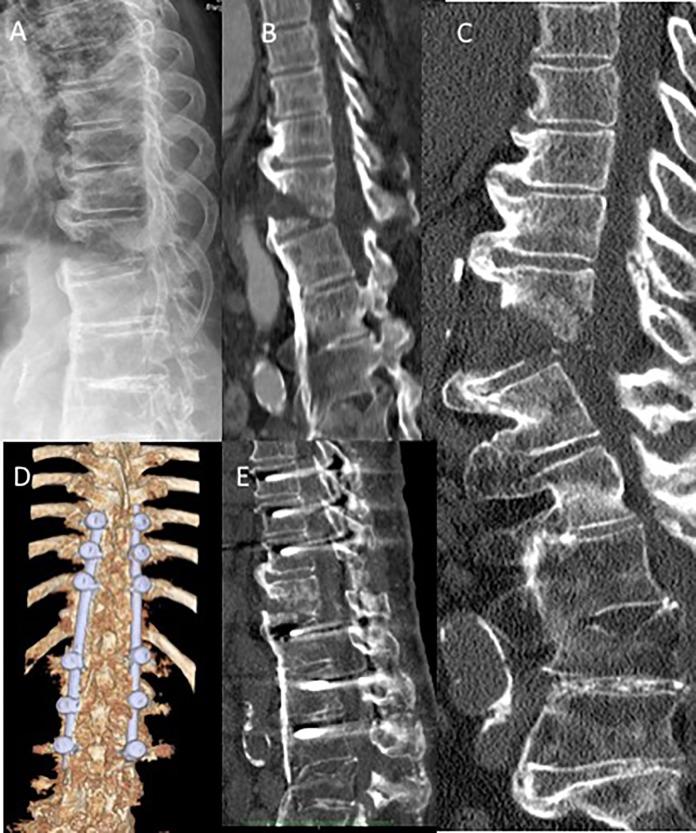

Nondisplaced fractures can be missed easily using conventional X-rays. Thus, computed tomography (CT) scans are recommended for all trauma patients with ASD. In doubt or presence of any neurologic involvement additional magnetic resonance imaging (MRI) scans should be obtained. Spine precautions should be maintained all times and until definitive treatment (<24 h). Nonoperative fracture treatment is not recommended given the mechanical instability of the most commonly seen fracture patterns (AOSpine B- and C-type, M2) in patients with ASD and inherent high risk of secondary neurologic deterioration. For patients with ankylosing spondylitis (AS) or diffuse idiopathic hyperostosis (DISH) sustaining cervical spine fractures, a combined anterior-posterior instrumentation for fracture fixation is recommended. Closed reduction and patient positioning can be challenging in presence of preexisting kyphotic deformities. In the thoracolumbar (TL) spine, a posterior instrumentation extending 2 to 3 levels above and below the fracture level is recommended to maintain adequate reduction and stability until fracture healing. Minimally invasive percutaneous pedicle screws and cement augmentation can help to minimize the surgical trauma and strengthen the construct stability in patients with diminished minor bone quality (osteopenia, osteoporosis).

使用传统X线片容易漏诊无移位骨折。因此,建议对所有患有ASD的创伤患者进行计算机断层扫描(CT)。如有疑问或存在任何神经受累情况,应额外进行磁共振成像(MRI)扫描。应始终采取脊柱防护措施,直至确定治疗(<24小时)。鉴于ASD患者中最常见骨折类型(AOSpine B型和C型,M2)的机械不稳定性以及继发神经功能恶化的固有高风险,不建议采用非手术骨折治疗。对于患有强直性脊柱炎(AS)或弥漫性特发性骨肥厚(DISH)且发生颈椎骨折的患者,建议采用前后联合内固定进行骨折固定。在存在既往驼背畸形的情况下,闭合复位和患者体位摆放可能具有挑战性。在胸腰椎(TL)脊柱,建议在骨折水平上下各延伸2至3个节段进行后路内固定,以维持充分复位和稳定性直至骨折愈合。微创经皮椎弓根螺钉和骨水泥强化有助于将手术创伤降至最低,并增强骨质量较差(骨质减少、骨质疏松)患者的内固定稳定性。